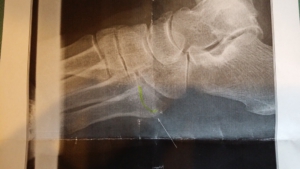

20150821_111235

第5中足骨基底部骨折が確認できました。